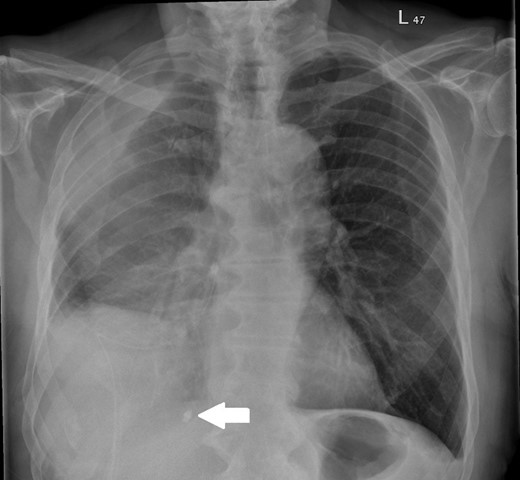

On assessment, he was found to have a right-sided pleural effusion and a right-sided 18 Fr Seldinger drain was inserted for diagnostic and therapeutic purposes. The insertion was difficult so the drain was withdrawn over the guidewire and removed. At this point, it was noted that the tip of the drain was missing. The patient was informed about this, retrieval of the foreign object was not attempted and the event was clearly documented. A new Seldinger drain was placed and the missing drain tip was visible on chest radiograph, see Fig. 1. Cessation of fluid output prompted drain removal and a computed tomography (CT) scan of the thorax was performed to further assess the pleural disease; this showed a large persistent multiloculated effusion.